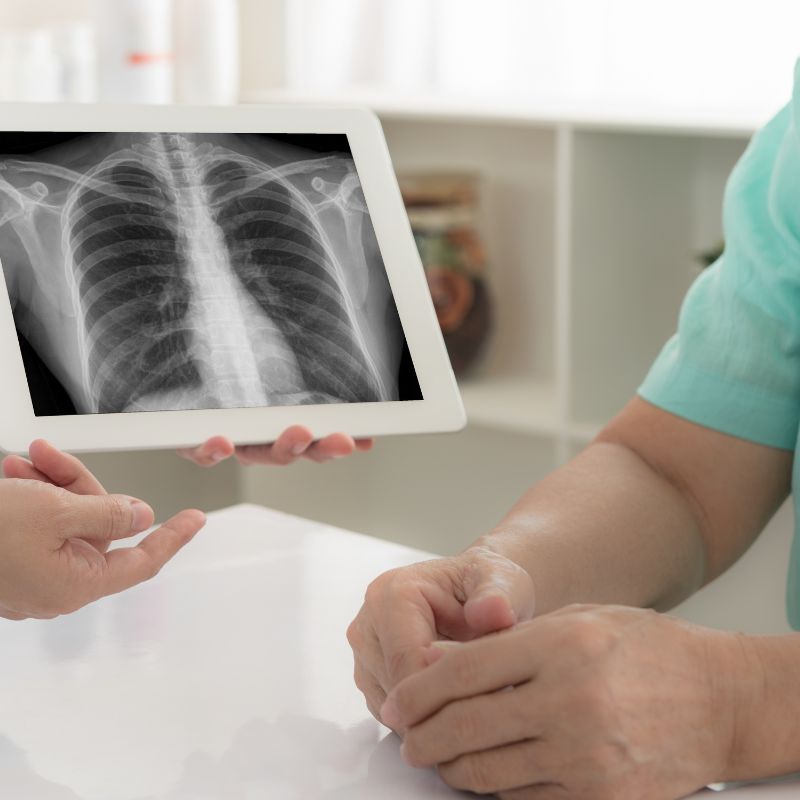

XPERT Home X-Ray

XPERT Home X-Ray

XPERT Home X-rays +Report Fees – Rs.999

Your doctor can request an X-ray from the comfort of your home at any time, 24 hours a day, seven days a week. Our team will visit your home to perform the X-ray and send the report directly to you and your doctor.

- On-demand home X-ray

- 24/7 X-ray service

- Certified radiology team

- Fast report delivery

- Doctor report coordination

- Safe digital imaging